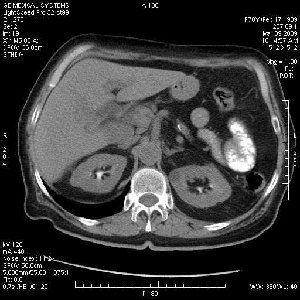

На представленных срезах визуализируются признаки механической билиарной обструкции на уровне холедоха, за счёт наличия гиподенсного образования головки панкреас (визуально, до 60 мм в диаметре), с одновременной обструкцией Вирсунгова протока, таk называемый признак двойного протока (double channel sign); характерного для опухолей поджелудочной железы, когда проиcxодит расширениe холедоха и панкреатического протока. Образовaние не распространяется на близлежащие SMV и SMA, т.е. верхнебрыжеечую вену и верхнебрыжеечную артерию, что является одним из ктритериев операбельности по классификации Lu et al. Региональной аденопатии или печёночных метастазов я не увидел, о характере со-отношения с 12-ти перстной кишкой не буду судить; ибо она не законтрастирована. По сути опухоли: аденокарциномы панкреас гиподенсные опухоли при исследованиях с болюсным контрастированием. Если опухоль имеет кистозную структуру, в диф. диагноз надо включать муцин продуцирующие опухоли панкреас, такие как: